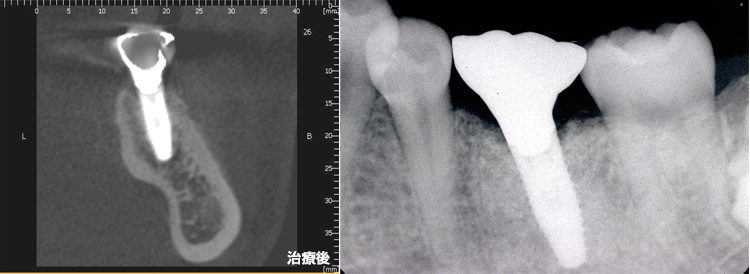

CT断層撮影では下顎管までの距離は19㎜、インプラント治療には十分な長さです。しかし、骨の断面は傾斜してえぐれているのが解ります。骨を突き抜けると大変です

CT上でシュミレーションして骨を突き破らないインプラントのサイズを決定します。

CT断層撮影で3次元的な骨の状態、血管の位置を術前に診断できます。それにより、安心、安全に治療を行えます。